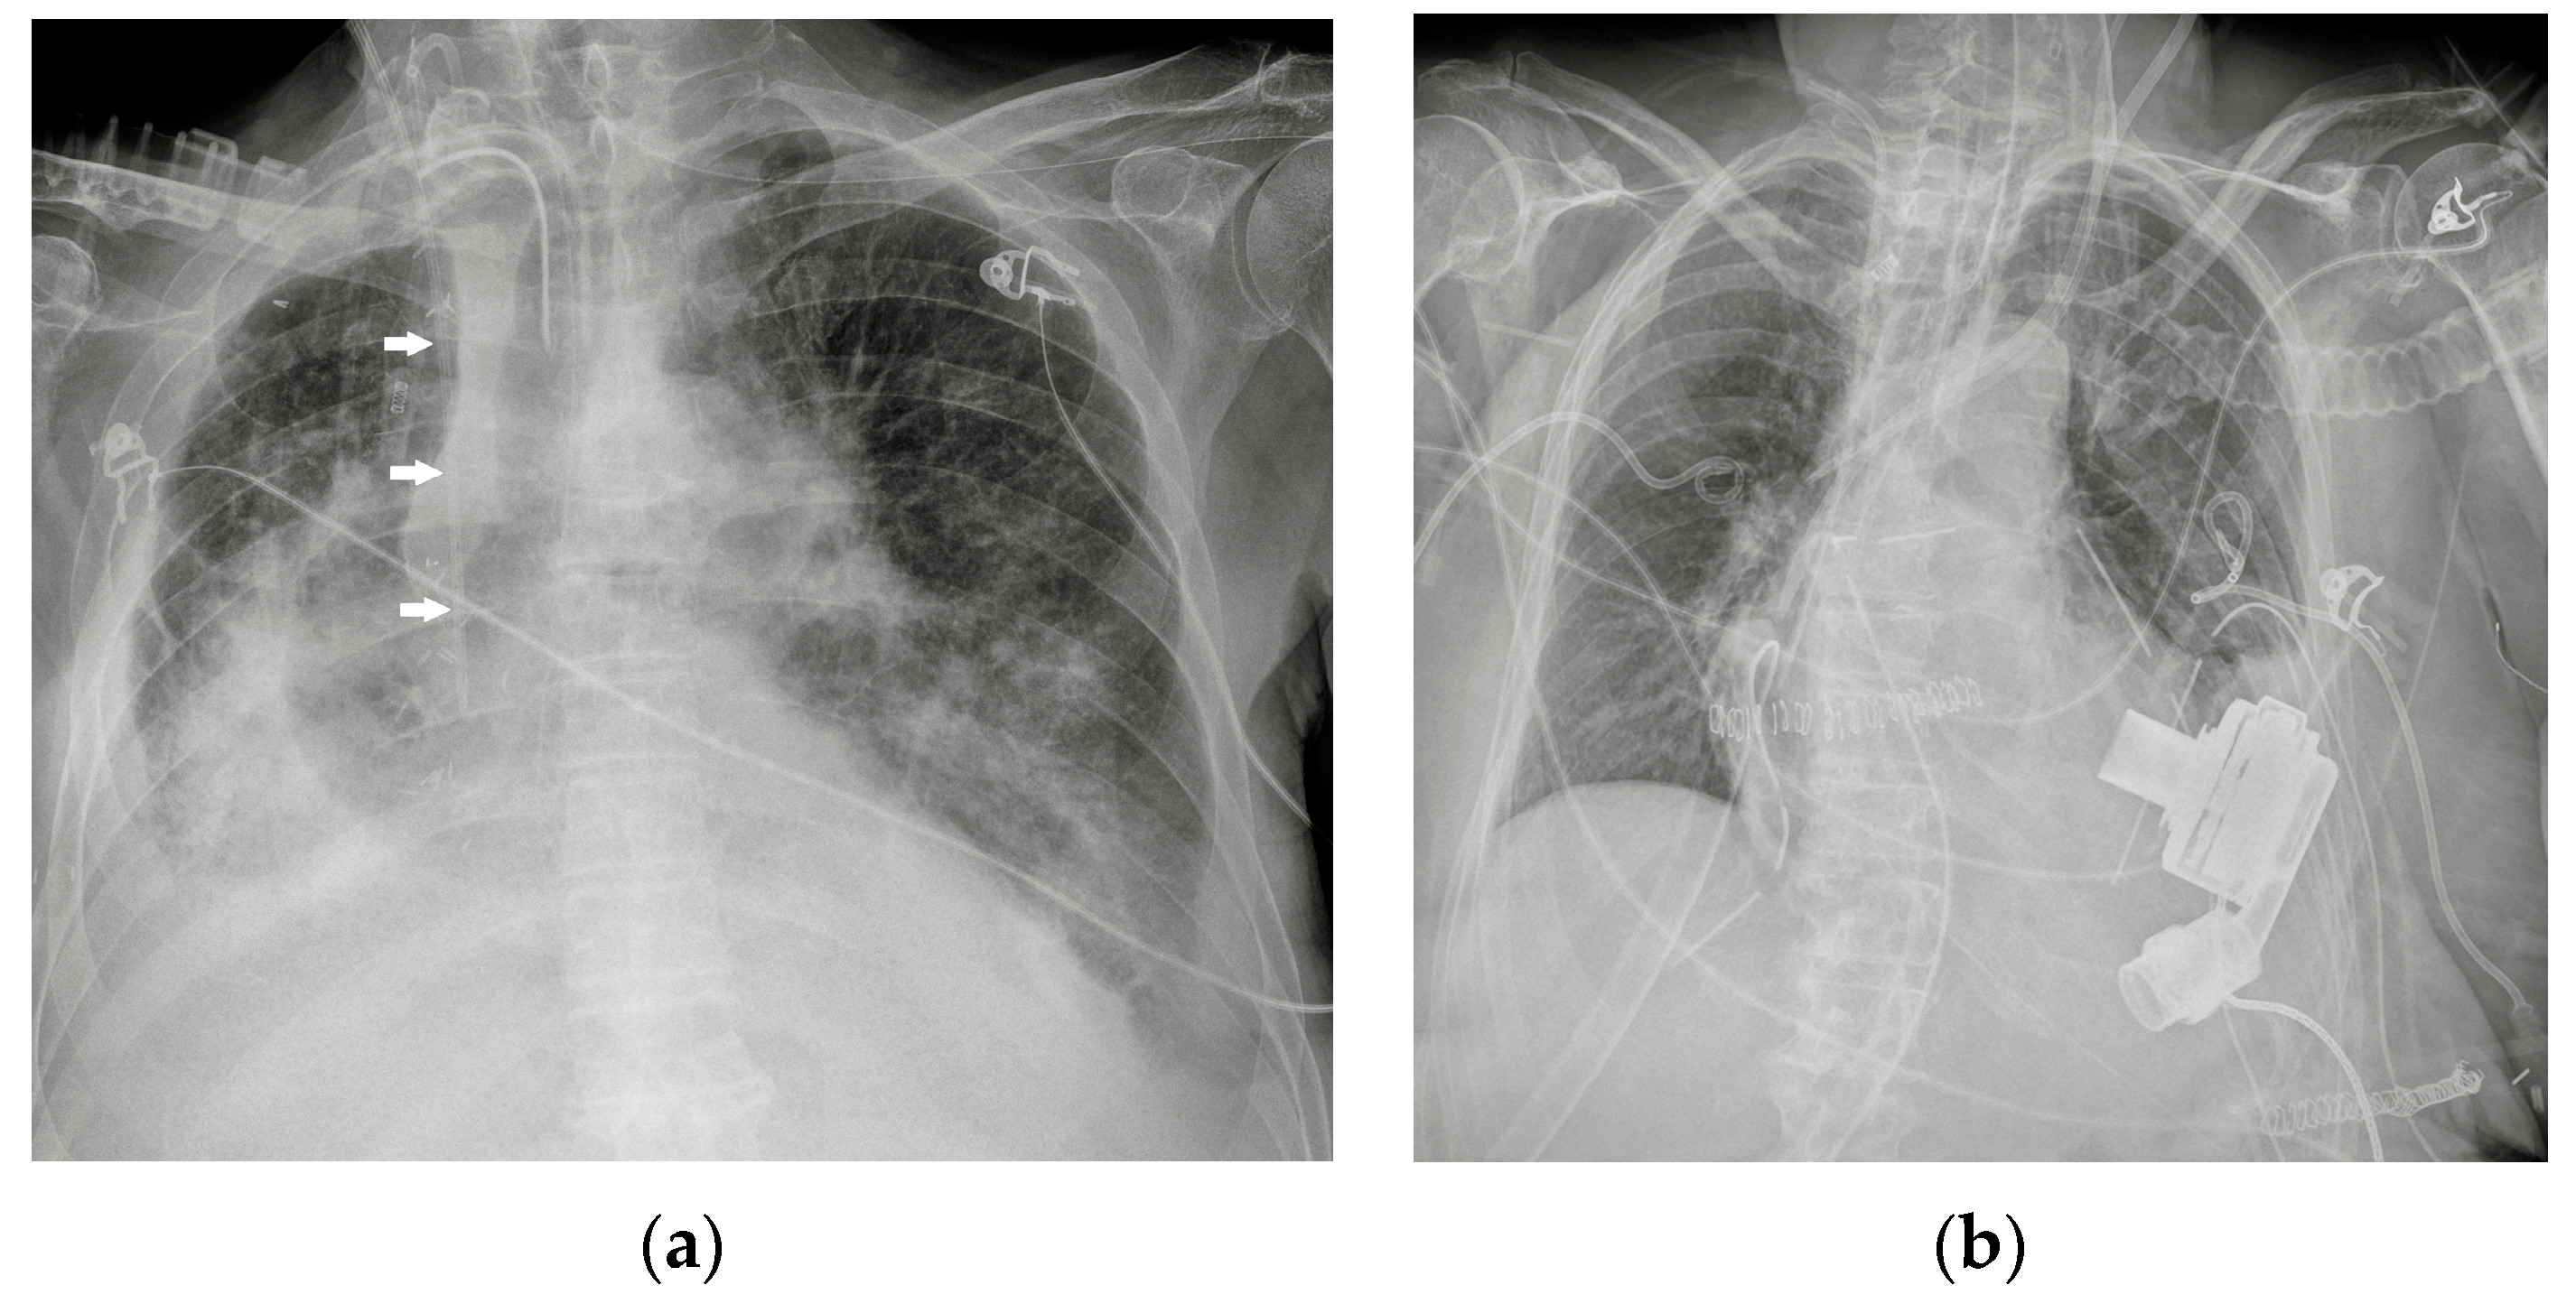

Potential confounding factors are EKGs’ leads, external tubes, artifacts and overlapping of different devices. The need to have at least two orthogonal projections to correctly locate a device can be a limit in patients in which only an anteroposterior projection is feasible. Moreover, technical factors must be considered, such as the orientation of the X-ray tube and patient rotation (Figure 1) [2].

Figure 1.

Potential confounding factors when checking for devices on a CXR. (a) Anteroposterior CXR of a right-sided rotated patient can simulate the dislocation of the central venous catheter (white arrows). (b) Anteroposterior CXR of a patient with multiple devices and external EKG leads.